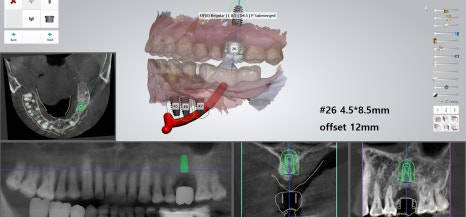

‘내비게이션 모의수술 프로그램’을 통해

치료 계획을 수립할 수 있겠습니다.

특히 아래에 지나가는

하치조 신경을 유의해야 됩니다.

왼쪽, 오른쪽 모두

아래턱 쪽으로 하치조 신경이 지나갑니다.

각 부위에 다수의 치아를 식립하게 될 경우

더욱이 심어야 될 위치나 깊이를

자세히 체크할 필요 있습니다.